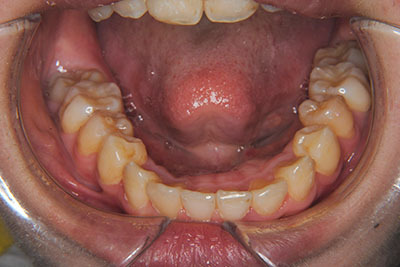

おとなの方でも矯正治療をあきらめないでください!

子供の頃に矯正治療を行う方が治療期間が短く済むというのは、確かですが、矯正治療は患者様の意識も重要です。

いくら歯が動き易くとも、本人がやる気でなければ効果は出ませんし、むし歯発生のリスクも高まります。おとなの方は顎の成長が終わっているため、治療の計画が立てやすいとも言えます。「もう大人だから…」とあきらめず、一度ご相談ください。